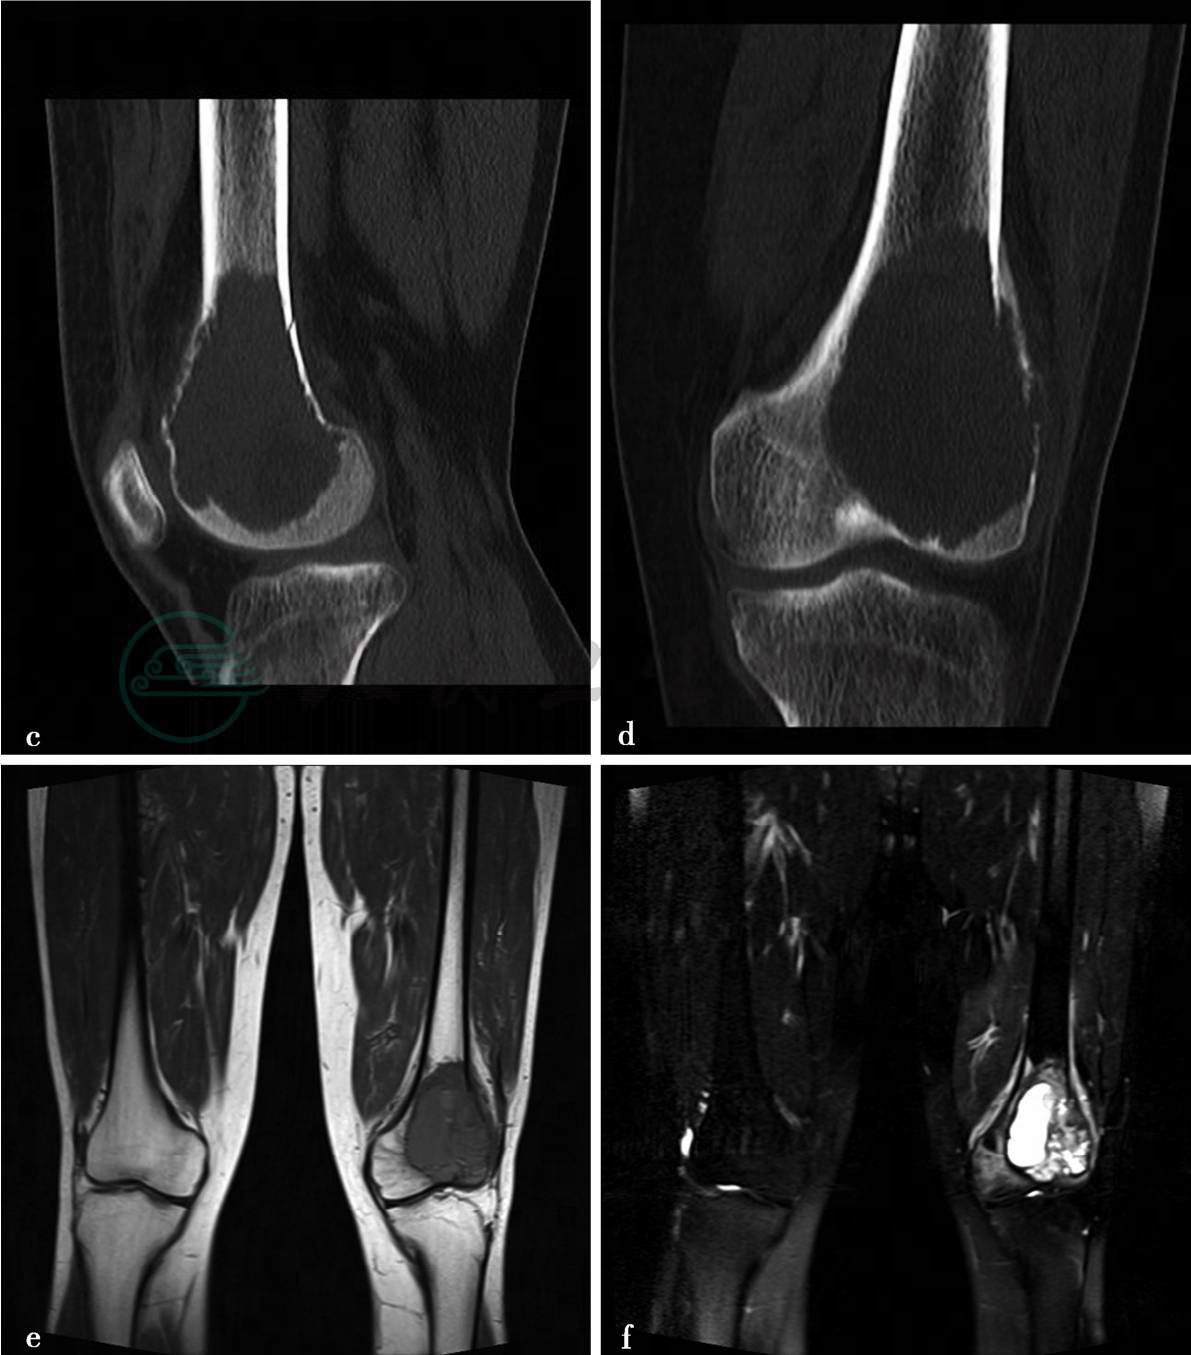

(2)病例2:

X线、CT平扫。

图2 图2a,X线示右股骨远端可见偏向股骨外侧髁的偏心性骨质破坏,病灶大小约6cm×6.5cm,边缘较清楚,无硬化边。病灶位于股骨远端,越过骨骺线,离关节面最近处约0.8cm。受累骨皮质完整,无骨膜反应。周围软组织清晰,无异常表现。图2b、c,CT示右股骨远端偏心性骨质破坏,病灶大小约6cm×6.5cm,略成膨胀性改变,边缘较清无硬化边,密度较均匀,CT值约35HU。后外侧骨皮质部分缺损,病灶内组织通过破损的皮质向后侧突出。无骨膜反应